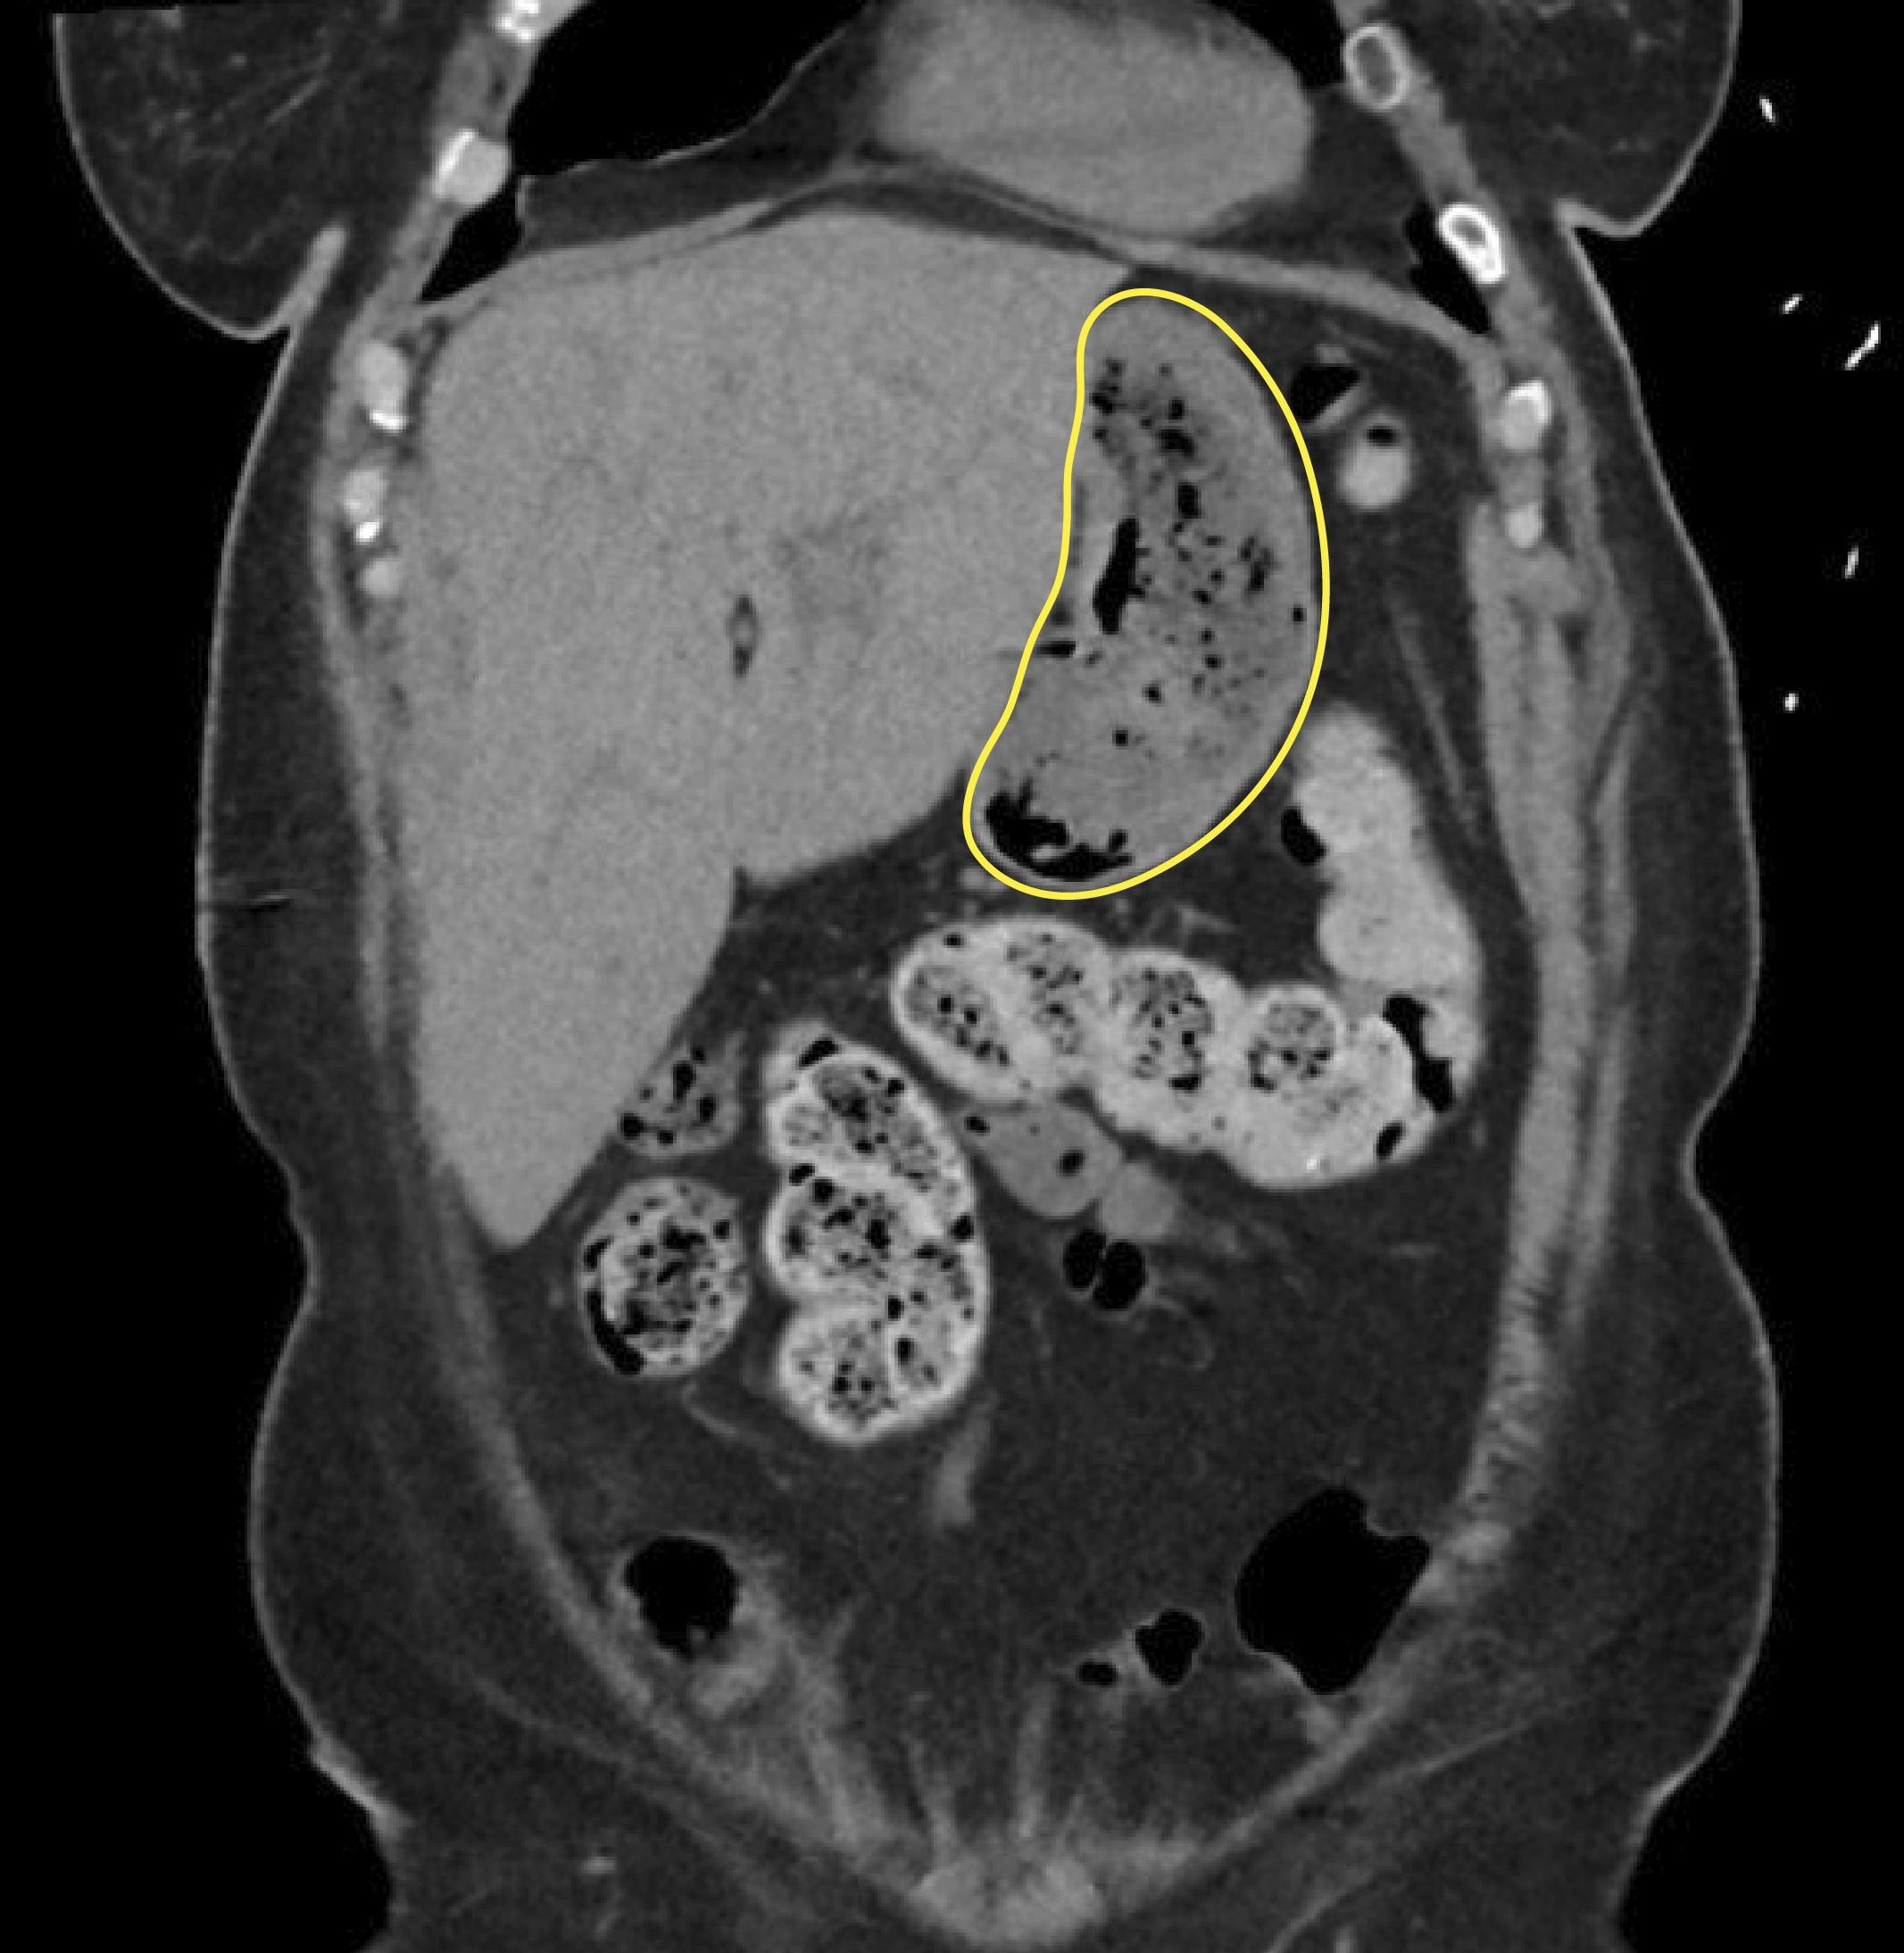

Сканирование с помощью неинвазивного метода МРХПГ (магнитно-резонансная холангиопанкреатография) выявило в желудке образование, похожее на скопление воздуха. А во время эндоскопии врачи обнаружили безоар — комок инородных тел, в данном случае остатков пищи, которые не смогли перевариться и, уплотнившись, превратились в так называемый желудочный камень. Он и стал причиной тошноты, рвоты и боли в животе.